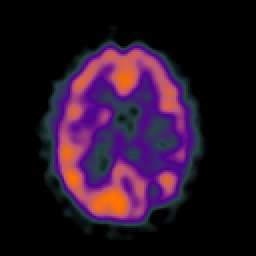

SPECT TC Study #5 -- Slice #33

[Home][Help][Clinical][Tour 1][Tour 2][Tour 3] Slice 33